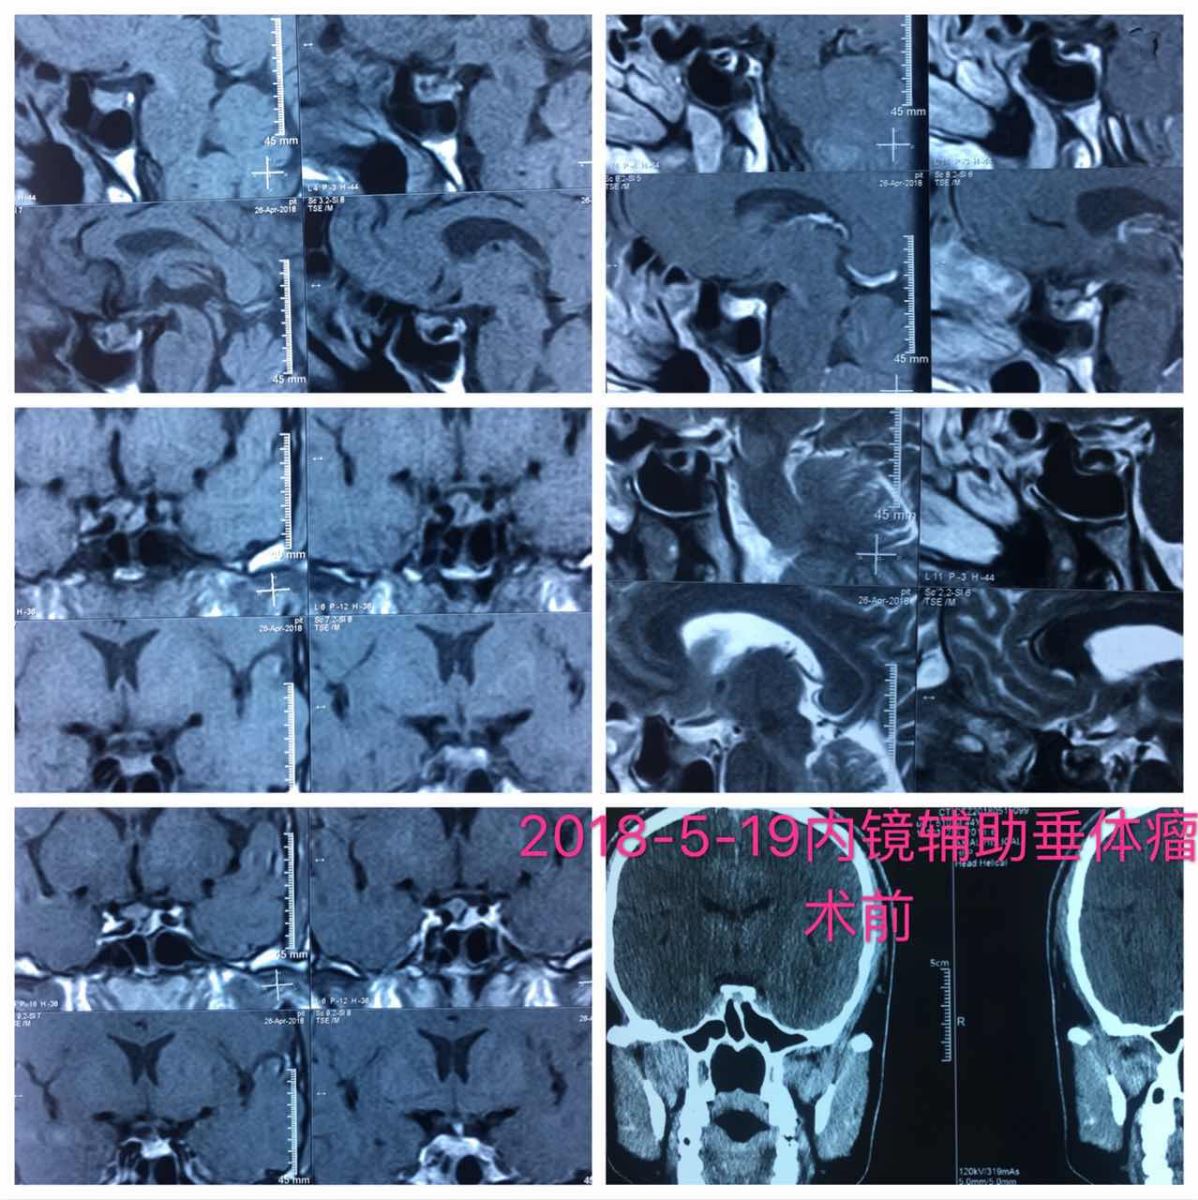

患者张先生,因“四肢末端胀木感3月余”入院,术前诊断为GH腺瘤,手术难度大,患者肿瘤边缘紧邻颈内动脉,部分包绕,通过神经内镜辅助,达到肿瘤全切。

影像图片

与传统显微镜下切除肿瘤不同,内镜下具有广角照明和全景视野,操作视野开阔,可360°全方位观察,光纤照明良好,同时可以通过内镜的进出调整与术野的距离,通过更换不同角度镜面的内镜能够更清晰的观察鞍底及其周围的解剖结构,准确进行术中定位,在切除肿瘤过程中能观察到鞍内及海绵窦侧壁的肿瘤切除情况,在一定程度上可提高肿瘤的全切率,降低因视野问题损伤颈内动脉、海绵窦、视神经、动眼神经等重要结构。

神经内镜不需要联合鼻窥镜进行手术,且神经内镜体积较小,对鼻中隔、鼻粘膜的损伤相对较小,可较好的保护鼻腔正常结构,术后嗅觉保留相对较好。